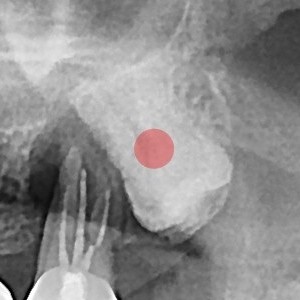

智齿拔除 完全埋伏智齿